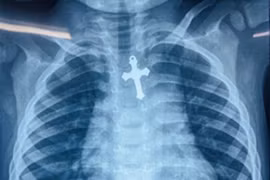

Bệnh viện Nhi Đồng 1, TPHCM vừa tiếp nhận một trường hợp nuốt dị vật đặc biệt nguy hiểm. Bệnh nhi là bé N.P.T., 3 tuổi, nuốt dị vật hình cây thánh giá nằm ở thực quản nguy cơ xuyên vào trung thất đe dọa tính mạng.